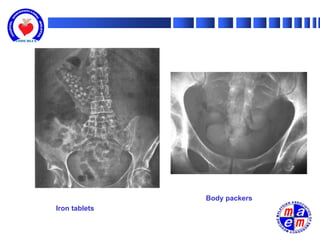

• Plain abdominal films: CHIPES (chloral hydrate, heavy

metals, iron, iodides, phenothiazines, enteric coated pills,

sustained-release preparations and solvents

Body packers

Iron tablets